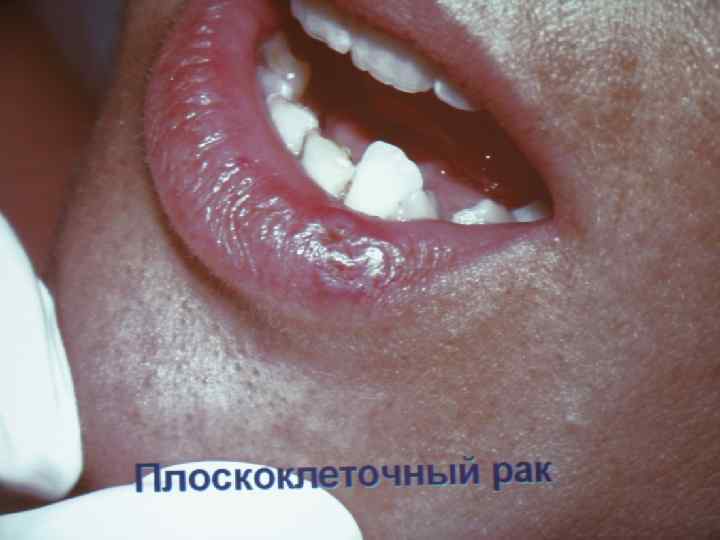

Общая характеристика опухолей полости рта Слизистая полости рта и подлежащие ткани представляют особую анатомическую сложность, обусловливающую специфику клинического течения и лечения развивающихся здесь опухолей. Это преимущественно различные виды плоскоклеточного рака – 90 -95%. В клинической практике приходится встречаться с многочисленными видами новообразований.

Общая характеристика опухолей полости рта Слизистая полости рта и подлежащие ткани представляют особую анатомическую сложность, обусловливающую специфику клинического течения и лечения развивающихся здесь опухолей. Это преимущественно различные виды плоскоклеточного рака – 90 -95%. В клинической практике приходится встречаться с многочисленными видами новообразований.

Рак слизистой оболочки щеки • Развивается на фоне лейкоплакии у курящих мужчин старше 50 лет; • Локализуется по линии смыкания зубов; • Рак переднего отдела протекает более благоприятно, чем заднего; • Морфологическая форма – плоскоклеточный рак; • Язвенно-инфильтративная или бородавчатая форма; • Метастазирует в нижнечелюстные и подбородочные лимфоузлы

Рак слизистой оболочки щеки • Развивается на фоне лейкоплакии у курящих мужчин старше 50 лет; • Локализуется по линии смыкания зубов; • Рак переднего отдела протекает более благоприятно, чем заднего; • Морфологическая форма – плоскоклеточный рак; • Язвенно-инфильтративная или бородавчатая форма; • Метастазирует в нижнечелюстные и подбородочные лимфоузлы